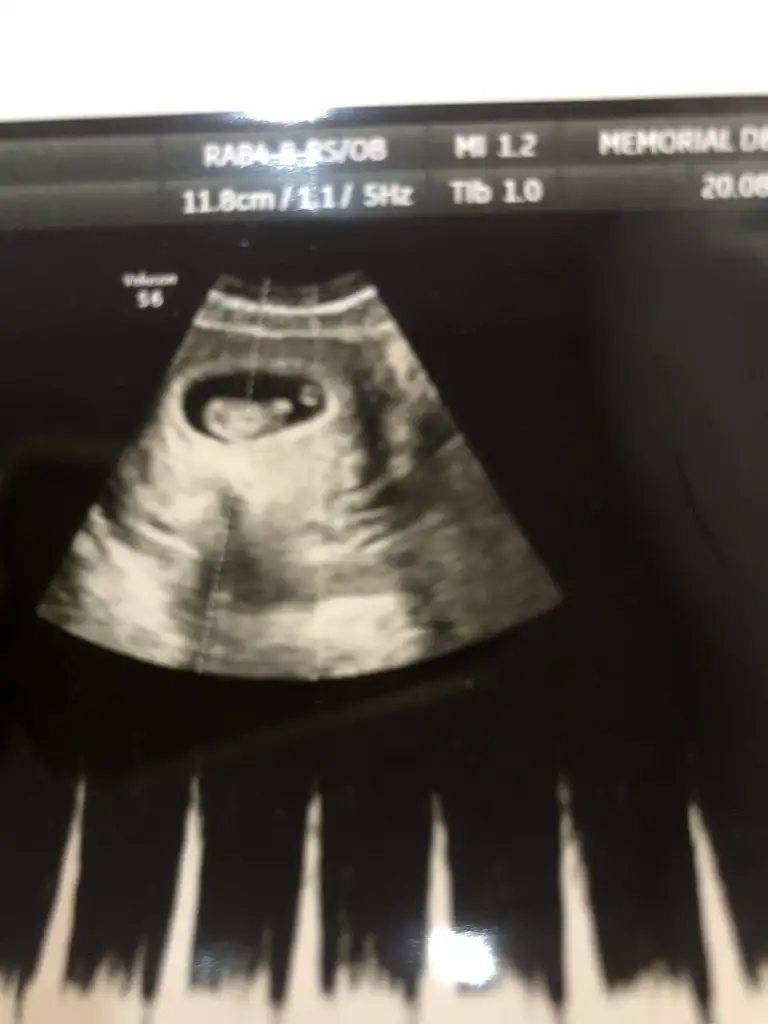

Erkek bebişMerhaba, 12. haftadan ultrason görüntülerimiz. Yorum yaparsanız çok sevinirim.Eki Görüntüle 2678844 Eki Görüntüle 2678845 Eki Görüntüle 2678846 Eki Görüntüle 2678844 Eki Görüntüle 2678845 Eki Görüntüle 2678846 Eki Görüntüle 2678844 Eki Görüntüle 2678845 Eki Görüntüle 2678846 Eki Görüntüle 2678846 Eki Görüntüle 2678844 Eki Görüntüle 2678845 Eki Görüntüle 2678846 Eki Görüntüle 2678844 Eki Görüntüle 2678845 Eki Görüntüle 2678846

Bana da öyle geldi bi de erkek olsa belli olurdu bu hafta dedi cogu kisi. Kız daha geç görünüyormuş bakalım ne cikacak iki hafta sonra yazarımKız gibi sanki